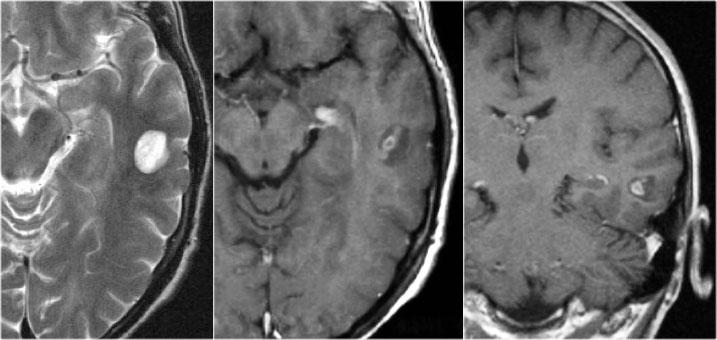

Hình ảnh T2W và FLAIR mặt phẳng coronal cho thấy xơ cứng thùy thái dương trong bên phải.

Lưu ý tình trạng mất thể tích, biểu hiện của teo não, gây giãn thứ phát sừng thái dương của não thất bên.

Tín hiệu cao trong hải mã phản ánh tình trạng gliosis.

Hình ảnh cho thấy xơ cứng thùy thái dương trong với hải mã tăng tín hiệu và teo nhỏ (mũi tên đỏ), kèm theo giãn thứ phát sừng thái dương trái của não thất bên trái.

Cũng cần lưu ý tình trạng tăng tín hiệu dưới vỏ não kết hợp ở thùy thái dương trái, gợi ý loạn sản vỏ não khu trú.

Xơ cứng thùy thái dương trong bên trái. Gliosis kín đáo của hải mã trái (mũi tên xanh dương) và teo não (mũi tên vàng).

Bệnh nhân 35 tuổi với động kinh thùy thái dương kháng trị.

MRI cho thấy tăng tín hiệu kín đáo của hải mã trái trên chuỗi xung FLAIR axial (mũi tên xanh dương) và teo hải mã trái trên hình ảnh coronal (mũi tên vàng).

Bệnh nhân được điều trị thành công bằng phẫu thuật cắt hạnh nhân – hải mã bên trái.